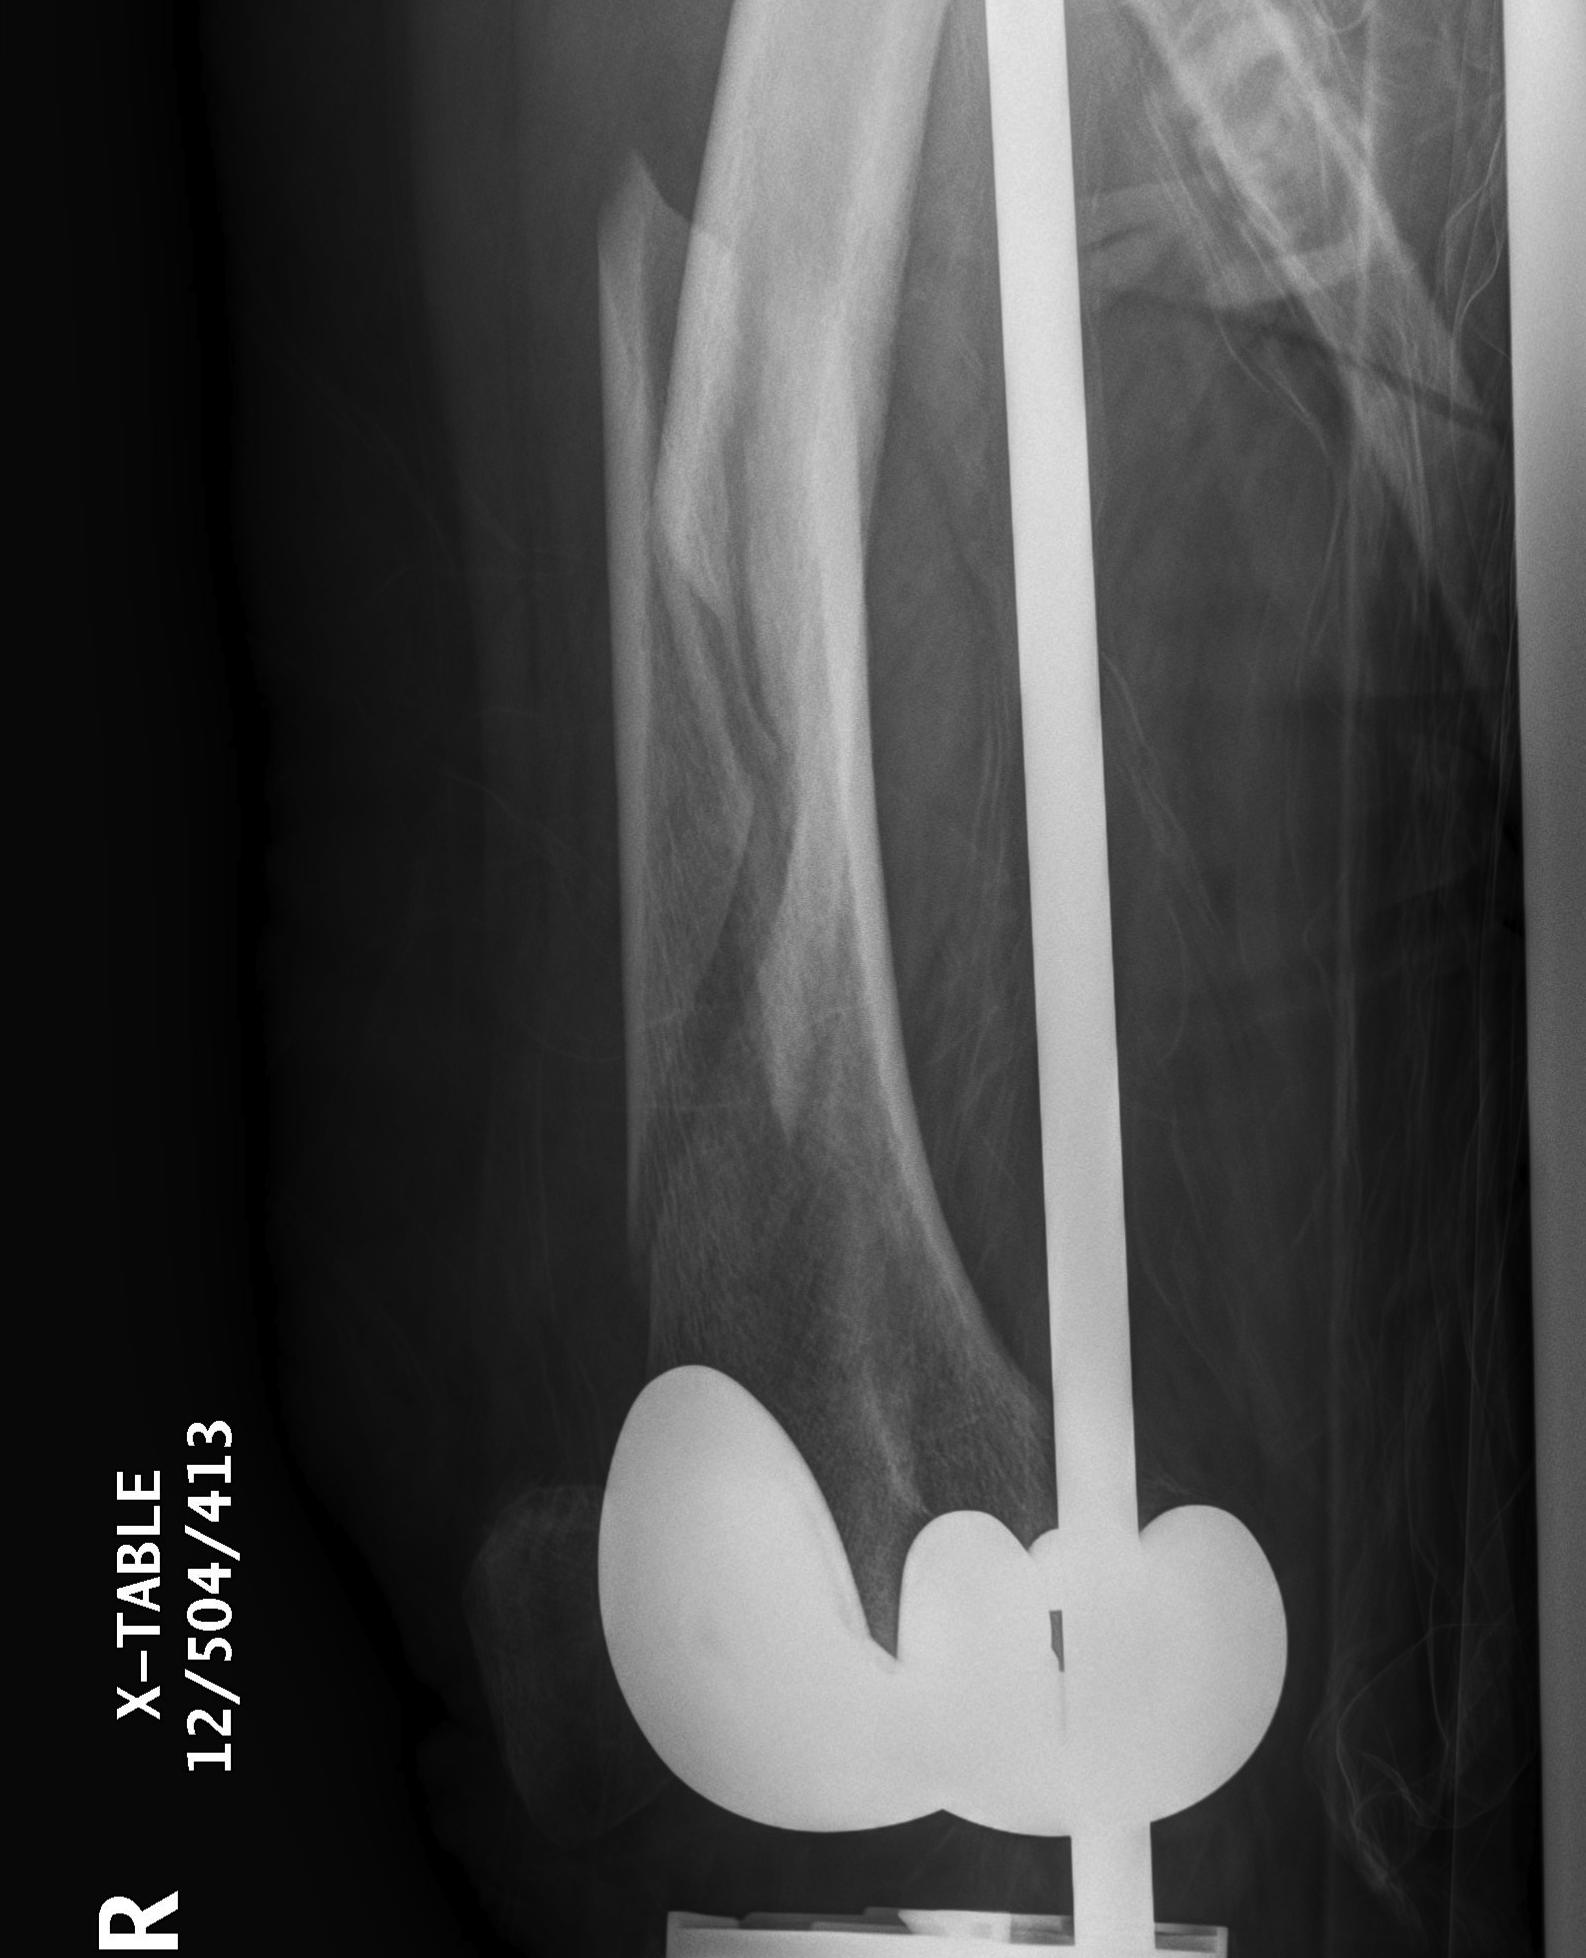

TKR Femoral Shaft Fracture IM Rod

3.  Anterograde nail

Indications

- sufficient bone above implant for distal locking

Issues

- stress riser between femoral implant and nail

- must ensure correct alignment

TKR Femoral FractureTKR Femoral Nail APTKR Femoral Nail Lateral